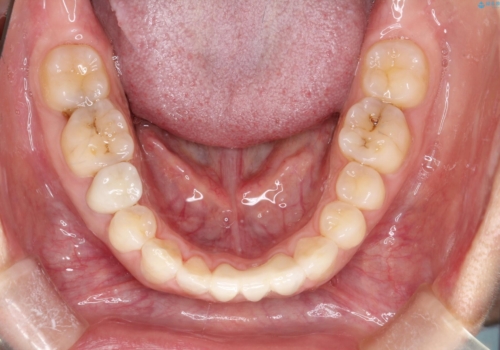

短期間での治療終了を希望され、ワイヤー矯正にて治療を行い1年ほどで治療を終了しております。

下顎前歯は矯正後補綴治療を行なっております。

期間や仕上がりで大変満足していただきました。

空隙歯列は後戻りしやすいため、長期間の保定が必要となります。